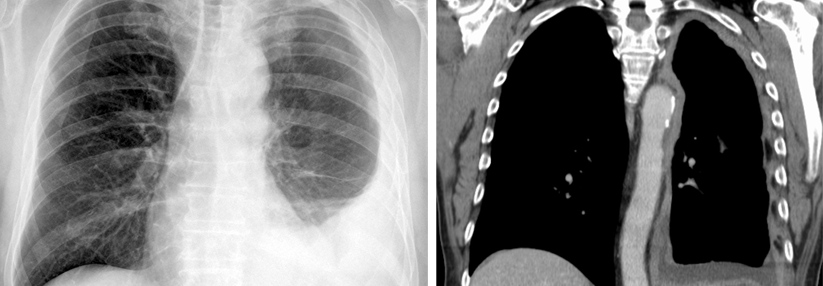

Der derzeitige Erstlinienstandard Nivolumab plus Ipilimumab ist beim Pleura-Mesotheliom zwar nur für begrenzte Zeit wirksam, gestattet aber immerhin der Hälfte der Patient:innen eine Zweitlinientherapie. Weitere Daten legen nahe, dass sich TROP-2 als neues therapeutisches Zielmolekül für Personen mit diffusem Mesotheliom anbietet.

Das lokalisierte, aber nicht resezierbare Pleura-Mesotheliom wurde bis vor wenigen Jahren mittels einer Platin-Pemetrexed-Chemotherapie behandelt, bis die Kombination aus Nivolumab und Ipilimumab diese ersetzte. Die Chemotherapie gilt seither als Zweitlinienoption. Während nach einer Erstlinien-Chemo etwa 37–47 % der Patient:innen noch eine zweite Behandlungslinie erhalten konnten, lag dieser Anteil nach der Erstlinien-Immuntherapie in CheckMate-743 bei 44,9 %. Wie hoch er in der Praxis außerhalb von Studien ist, war bislang unbekannt.